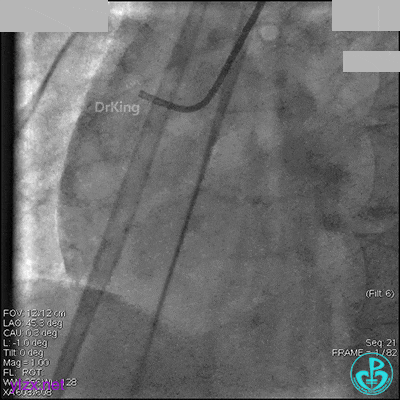

AL 1.0指引导管到位,简单短时尝试导丝不能顺利通过前降支或回旋支病变。改变策略处理右冠脉病变,计划植入2枚支架。AL指引导管到位,Sion blue导丝到达右冠脉远端。导丝通过后1.5mm及2.5mm球囊14~16atm充分扩张中段病变。

右冠脉中段充分扩张后欲植入3.5×38mm支架时,支架难以通过中远段扭曲处,且指引导管、导丝弹出飞扬。反复尝试导丝重新到达右冠脉远端时通过不顺利,局部造影剂滞留,远端血流接近3级。